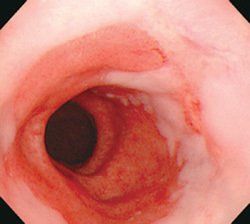

2.食管鏡檢查

典型的Barrett食管是在胃食管交界上方出現紅色的柱狀上皮區,部分患者可見反流性食管損傷的徵象。活檢可證實並找到柱狀上皮化生。